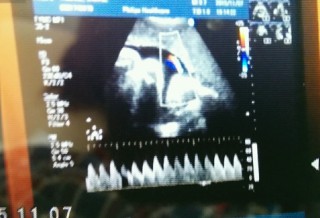

35w0d頭81.2㎜お腹311㎜大腿骨62.3㎜体重2377g やっぱりちょっとおなかがデブ(T.T)。 今回は胎児スクリーニングの結果説明を医師から丁寧にしてもらい、主人も私もとても安心できました(^^)出血がまだあったり不安はかかえてますが、赤ちゃんは元気にぐんぐん育ってくれてるのでホッ(*^^*) もう少しだね♪ ※写真はへその緒の動脈波形です。